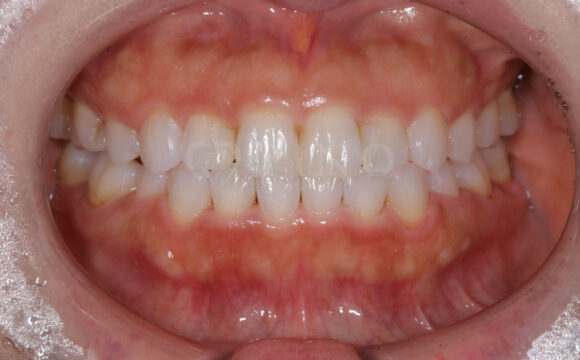

症例3:ワイヤー矯正後の後戻りが気になる(40代女性)

主訴 ワイヤー矯正後の後戻りが気になる 診断名 叢生 治療方法 マウスピース部分矯正 抜歯 なし オルソパルス なし 治療期間 9ヶ月 費用 436,000円 副作用・注意点 矯正後の後戻りを防ぐためリテーナーの使用が必要となる 備考 奥歯に噛み合わせ不良がない場合、部分矯正が適応となる -